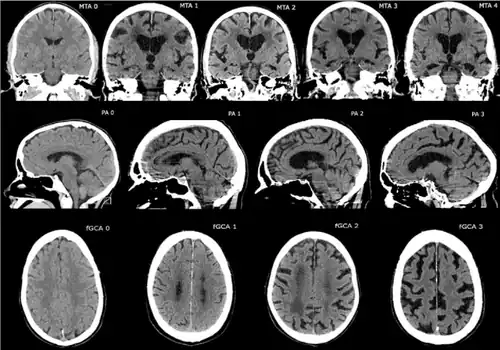

%252C_posterior_atrophy_(PA)_and_frontal_cortical_atrophy_(fGCA).png)

- Medial temporal lobe atrophy (MTA)

- Posterior atrophy (PA)

- Frontal cortical atrophy (fGCA)

CT and MRI are most commonly used to observe the brain for cerebral atrophy. A CT scan takes cross sectional images of the brain using X-rays, while an MRI uses a magnetic field. With both measures, multiple images can be compared to see if there is a loss in brain volume over time.[20]